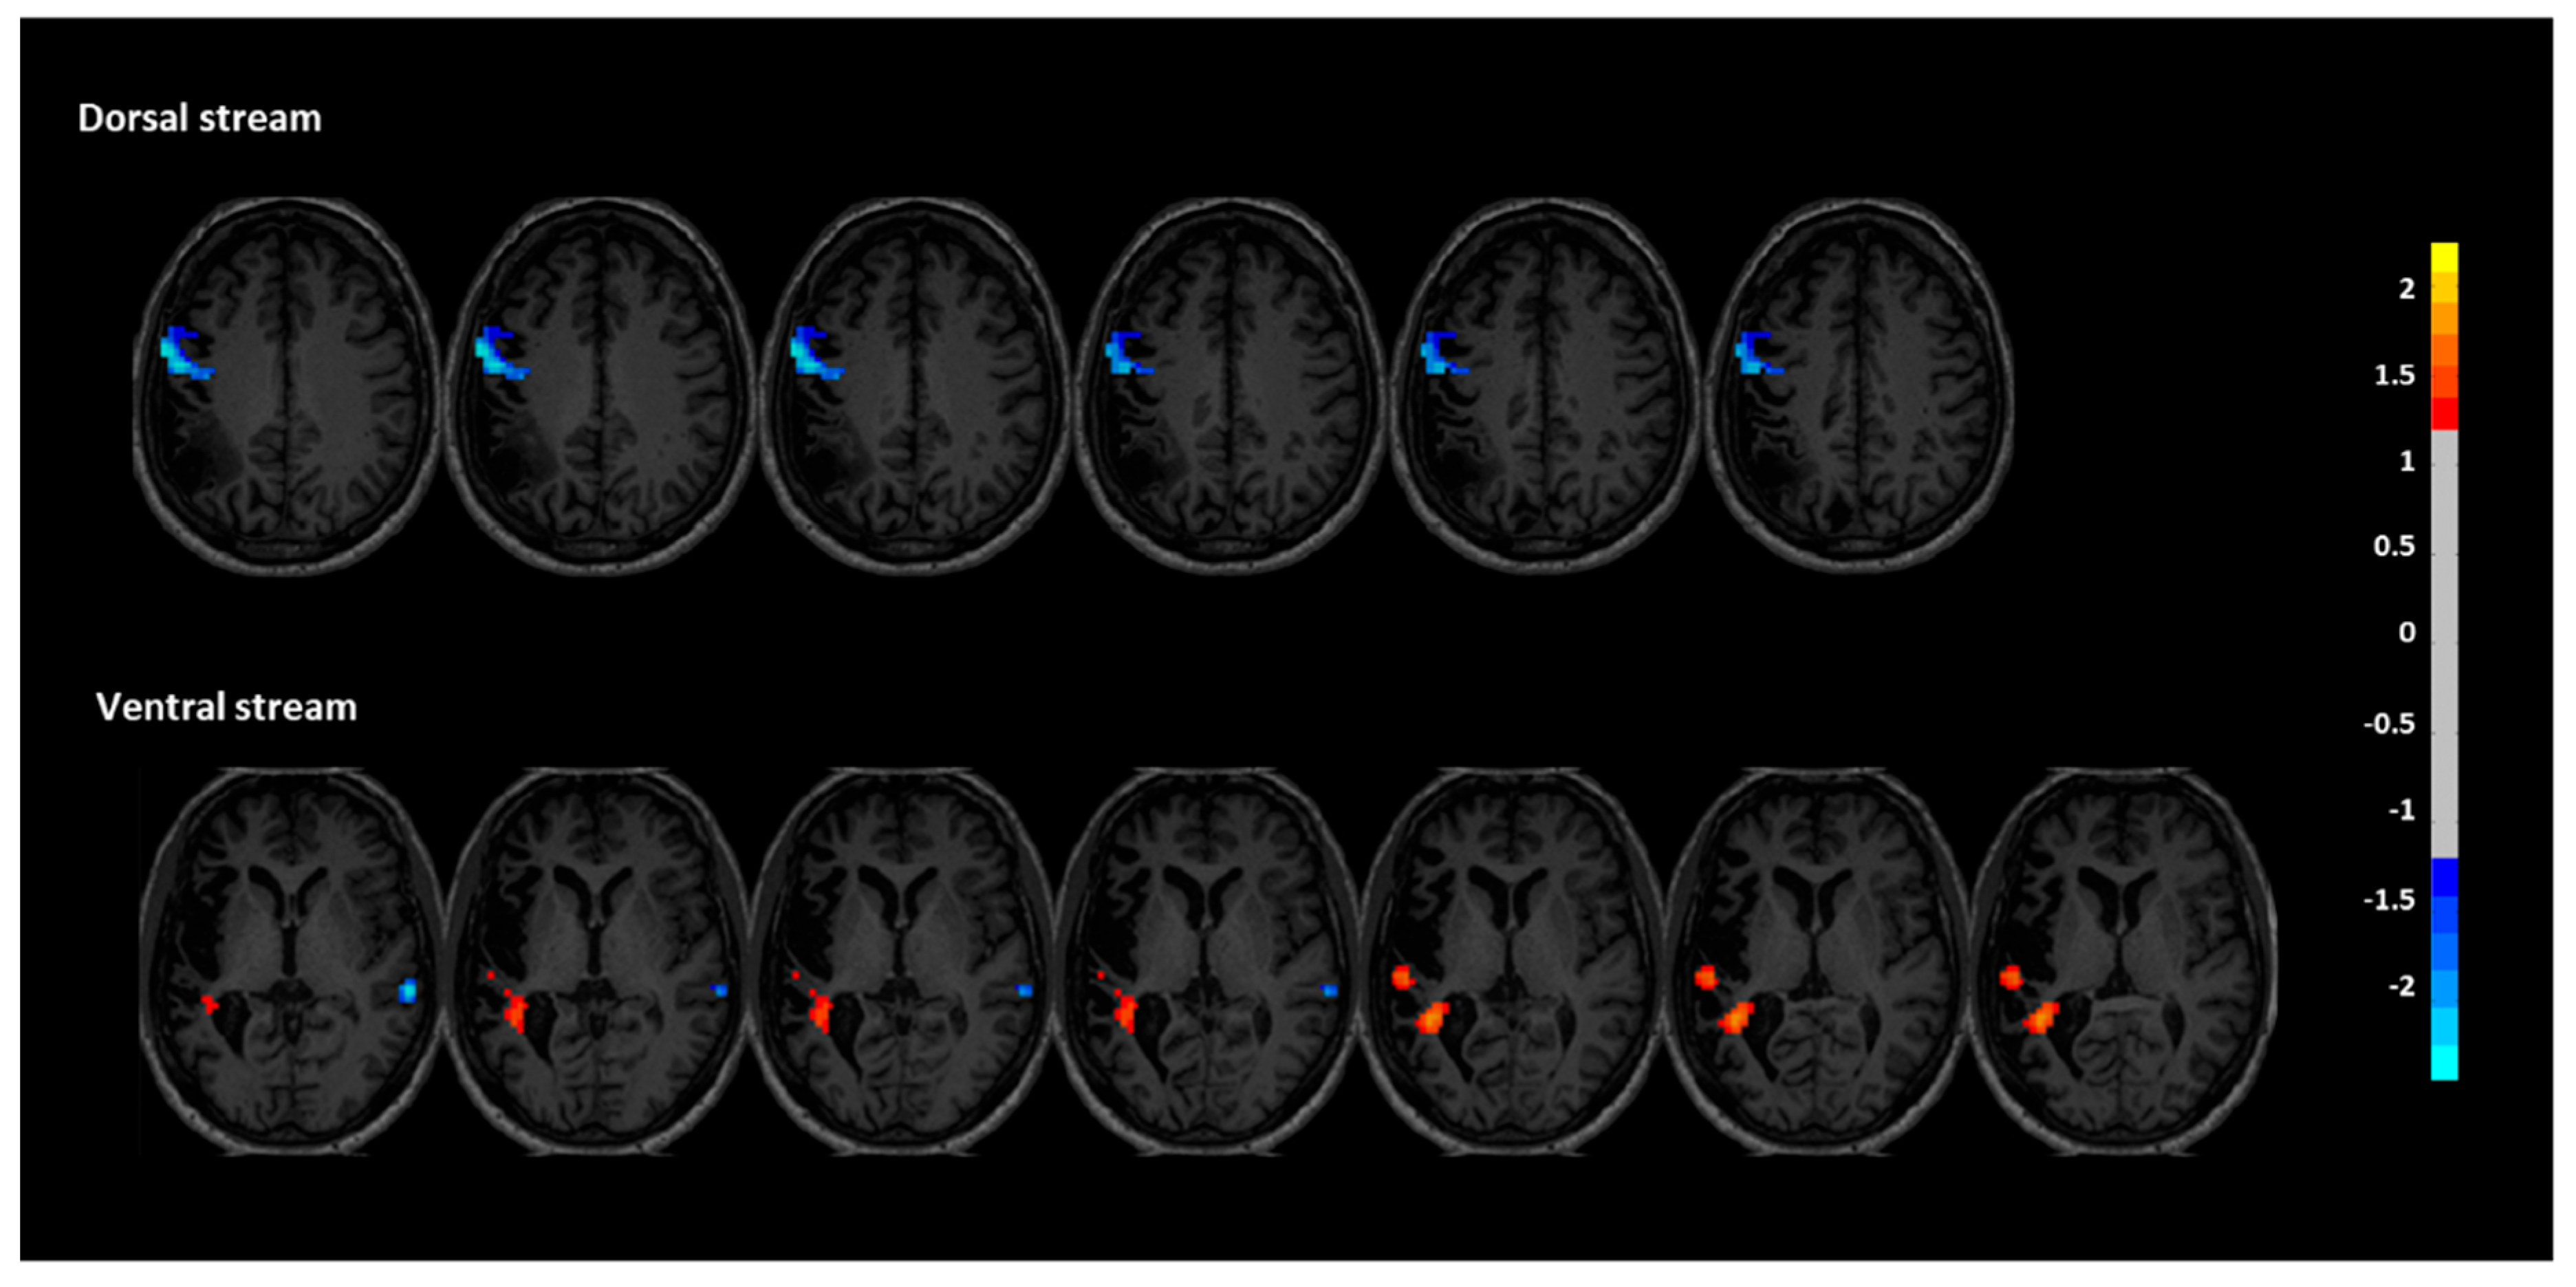

3.2. Resting-State fMRI